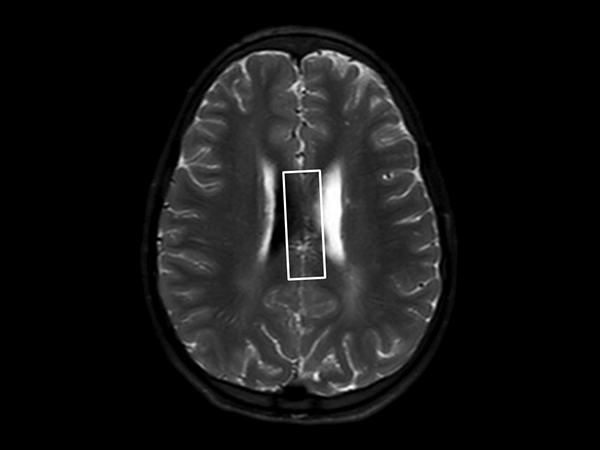

In this case, a 10-year-old girl thrown from a horse. The SWIp images provided increased visibility of the corpus callosum injury compared to the T2-weighted, diffusion weighted and gradient echo images, see the box in the images. SWIp also provides increased visibility of the cortical contusion (arrows) compared to gradient echo imaging. In this case, SWIp helped to characterize the extent of the patient’s injury, which is important to know for short term care and longer term prognosis and rehabilitation.

Axial T2w SSh TSE

Axial Diffusion (b1000)